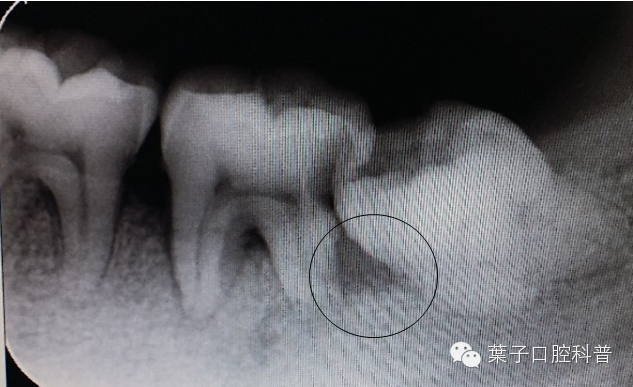

第二磨牙与智齿之间牙槽骨吸收